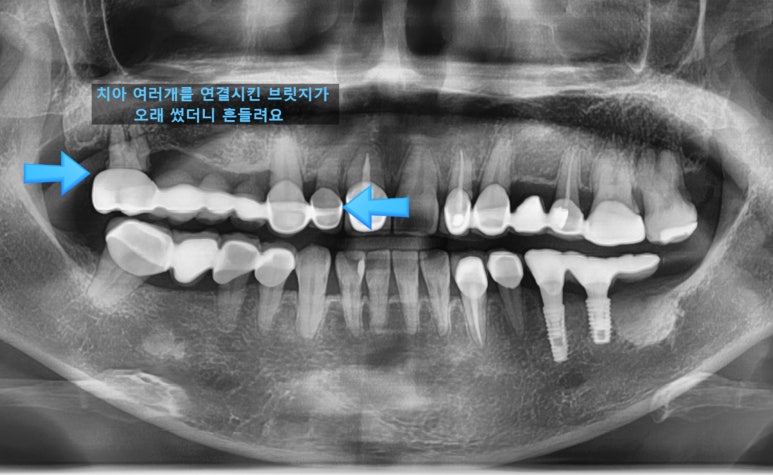

치아 여러개를 연결시킨 브릿지가 오래 되어서 흔들려요

라며 찾아오신 환자분입니다.

여러개 임플란트를 동시에 하는 수술이고

환자분도 겁이 많아 수술시간이 짧게 끝나는 걸 원하셔서

네비게이션 임플란트로 시행하여 빠른 시간에 수술을 끝낼 수 있었습니다.

상악동 거상술 뼈이식도 같이 진행하였습니다.